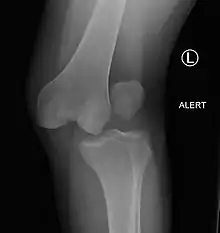

| Plain lateral X-ray of the left knee showing a posterior knee dislocation[1] | |

Plain X-rays, CT scan, ultrasonography, or MRI may help with the diagnosis.[2][10] Findings on X-ray that may be useful among those who have already reduced include a variable joint space, subluxation of the joint, or a Segond fracture.[5]

They may be divided into five types: anterior, posterior, lateral, medial, and rotatory.[4] This classification is based on the movement of the tibia with respect to the femur.[10] Anterior dislocations are the most common, followed by posterior dislocations.[2] They may also be classified based on what ligaments are damaged.[2]